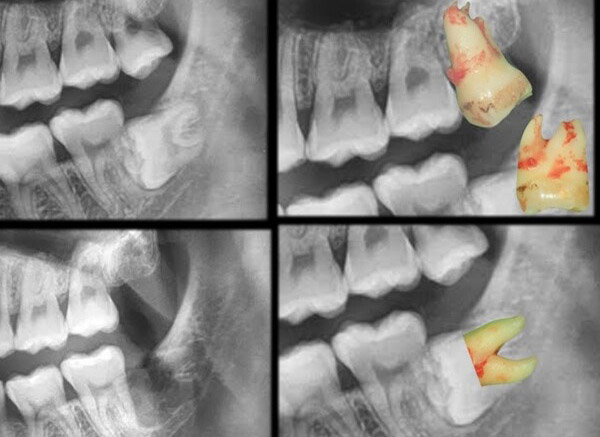

微創智齒手術案例分享